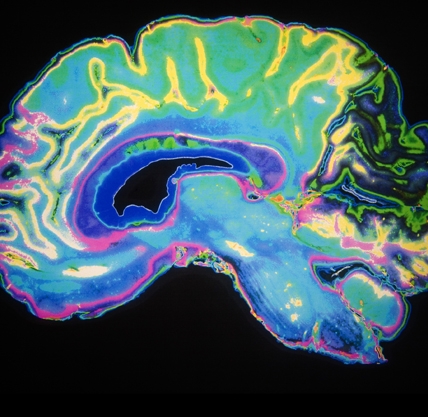

A sophisticated neuro-imaging method called diffusion tensor imaging (DTI) appears more sensitive than an MRI. In this study, DTI could detect changes in the brain right away (and months after) an injury when a conventional MRI of the same brain looked normal.